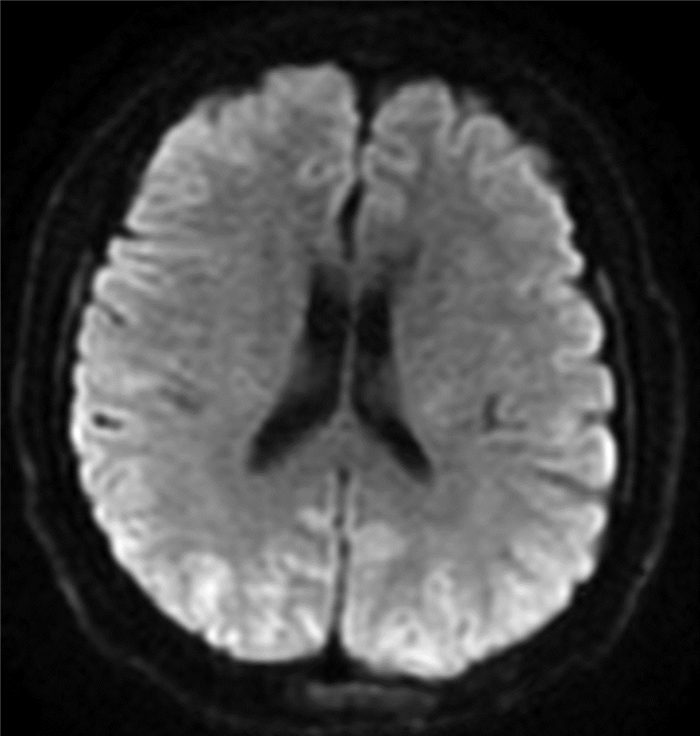

食管胃静脉曲张内镜下治疗后并发可逆性后部脑病综合征1例报告

于亭亭, 姜珊珊, 朱萌然, 白云

2022, 38(1): 177-179. DOI: 10.3969/j.issn.1001-5256.2022.01.030

摘要(807) HTML (197) PDF (3069KB)(54)

摘要: